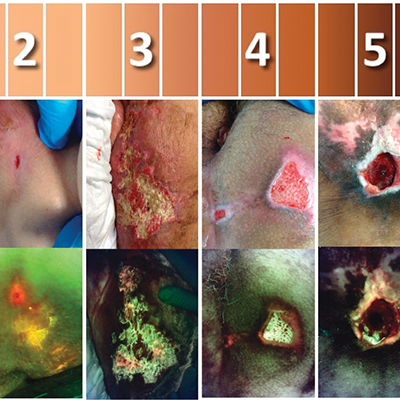

Skin Pigmentation Impacts the Clinical Diagnosis of Wound Infection: Imaging of Bacterial Burden to Overcome Diagnostic Limitations

Johnson J. et al. JREHD 2023

Bacterial Fluorescence Imaging to Address Racial Inequities in Wound Infection Assessment

Andersen, CA et al. Adv Skin & Wound Care 2024